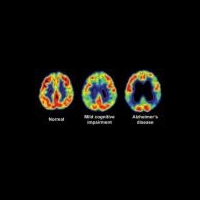

Раннее выявление болезни Альцгеймера

Группа финских исследователей разработала метод раннего выявления болезни Альцгеймера по анализу крови. Ученым удалось обнаружить признаки развития заболевания за пять лет до появления симптомов. Результаты их работы опубликованы 13 декабря в журнале Translational Psychiatry.

Болезнь Альцгеймера (старческое слабоумие) – неизлечимое дегенеративное заболевание. Как правило, оно обнаруживается у людей старше 65 лет и поначалу развивается практически бессимптомно. Первым симптомом болезни Альцгеймера считается потеря памяти, затем нарушается способность говорить и понимать сказанное, происходит потеря долговременной памяти, постепенное затухание функций организма, которое ведёт к смерти.